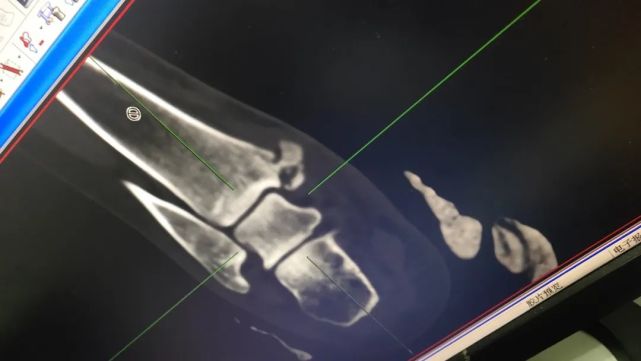

住院记得带好病历,影像片子(无论是胶片还是电子图像,如果是DICOM格式可能得带上笔记本),各种检查、检验报告。衣服不用带太多,甚至可以只带一套留着出院的时候穿就可以了,毕竟住院的时候每天都有阿姨来发干净的病号服。